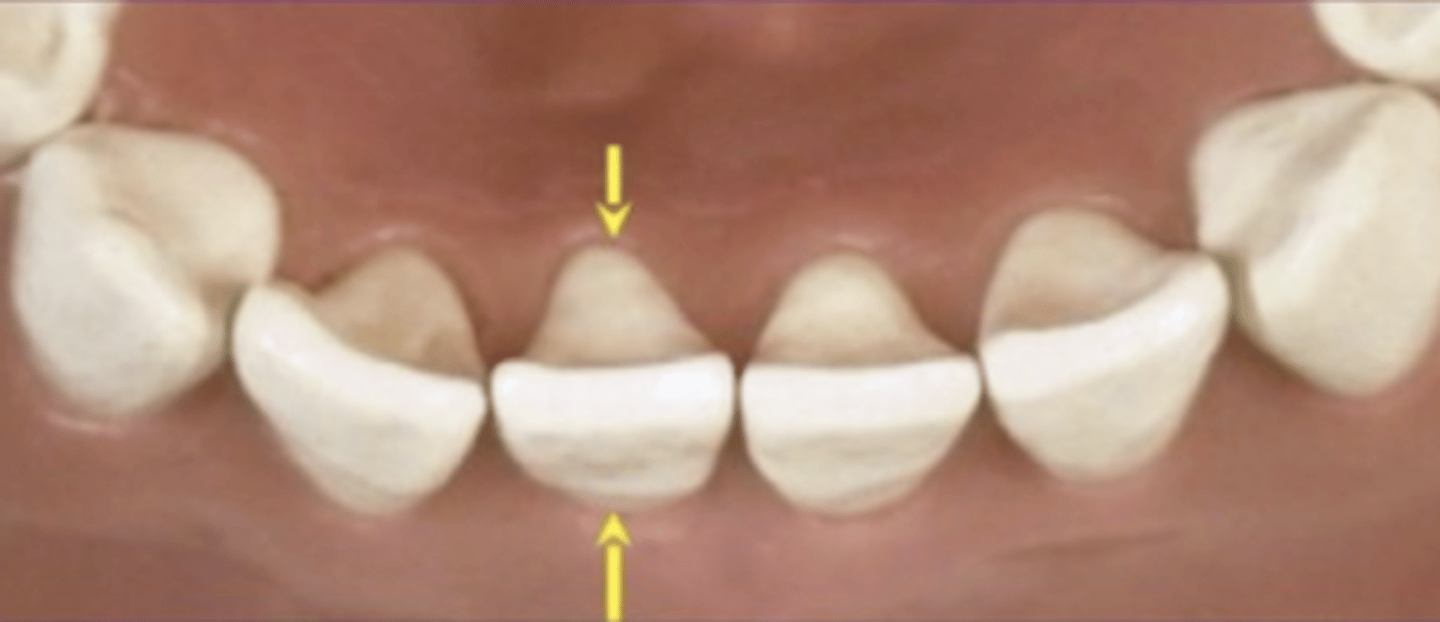

- Mamelons = 3 lobes on incisal edge

Mamelons

Wear Facets

Wear if the incisal edge